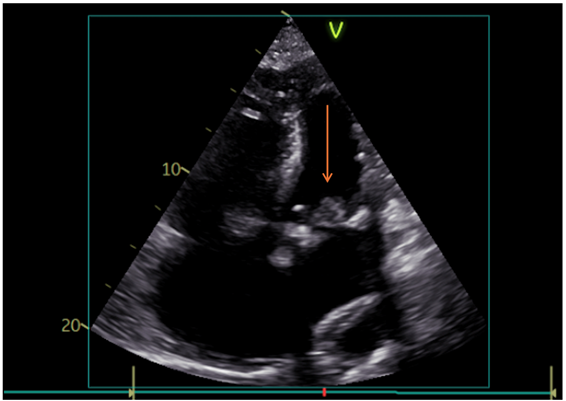

Given the increased risk of infective endocarditis, a transthoracic echocardiography was performed, revealing a preserved left ventricular ejection fraction of 50% and a mobile mass attached to the mitral valve (Figure 2). Transesophageal echocardiography (TOE) confirmed a 1.4x1.4cm vegetation causing significant stenosis (mean pressure gradient 10mmHg) and mild valvular regurgitation (Figure 3).

Figure 2: Vegetation on the bioprosthetic mitral valve as seen on transthoracic echocardiography on admission (arrow).